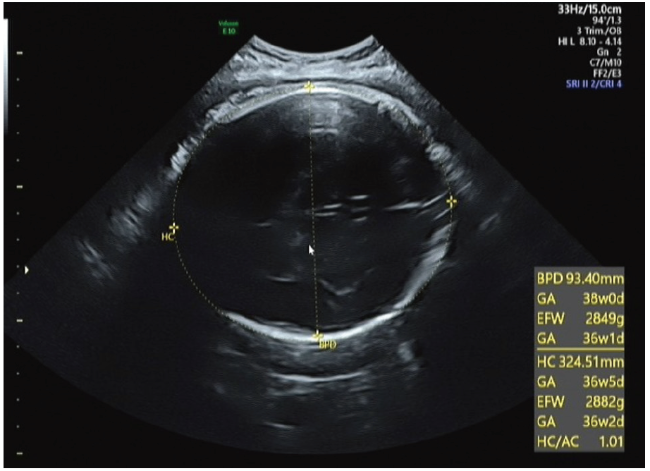

在产妇孕晚期常规超声中完成,测量采用美国GE Voluson E8或E9彩色超声诊断仪,探头型号C1-5-D,频率3~5 MHz。产妇呈仰卧位,呼吸平静。HC标准测量切面为胎头横切时的丘脑平面,测量近侧颅骨骨板外缘至远侧颅骨内缘间的距离,测量仪沿胎儿颅骨声像外缘直接测出HC,测量不包括颅骨外头皮等软组织[17],见图2

图2 HC的超声测量图像

Figure 2 Ultrasound measurement image of HC